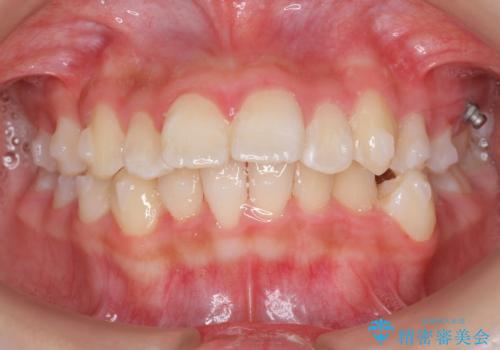

中学生のマウスピース矯正 歯を抜かずにキレイに

- 出っ歯を主訴に来院。

非抜歯ながらも、矯正用のインプラントを使用し、出来るだけ前歯を下げるように工夫して治療しました。

治療結果にはお母様、ご本人も含め、大変喜んでいただきました。

歯を抜かずに治療しましたが、治療前後で口元が悪化しないように治療することができました。